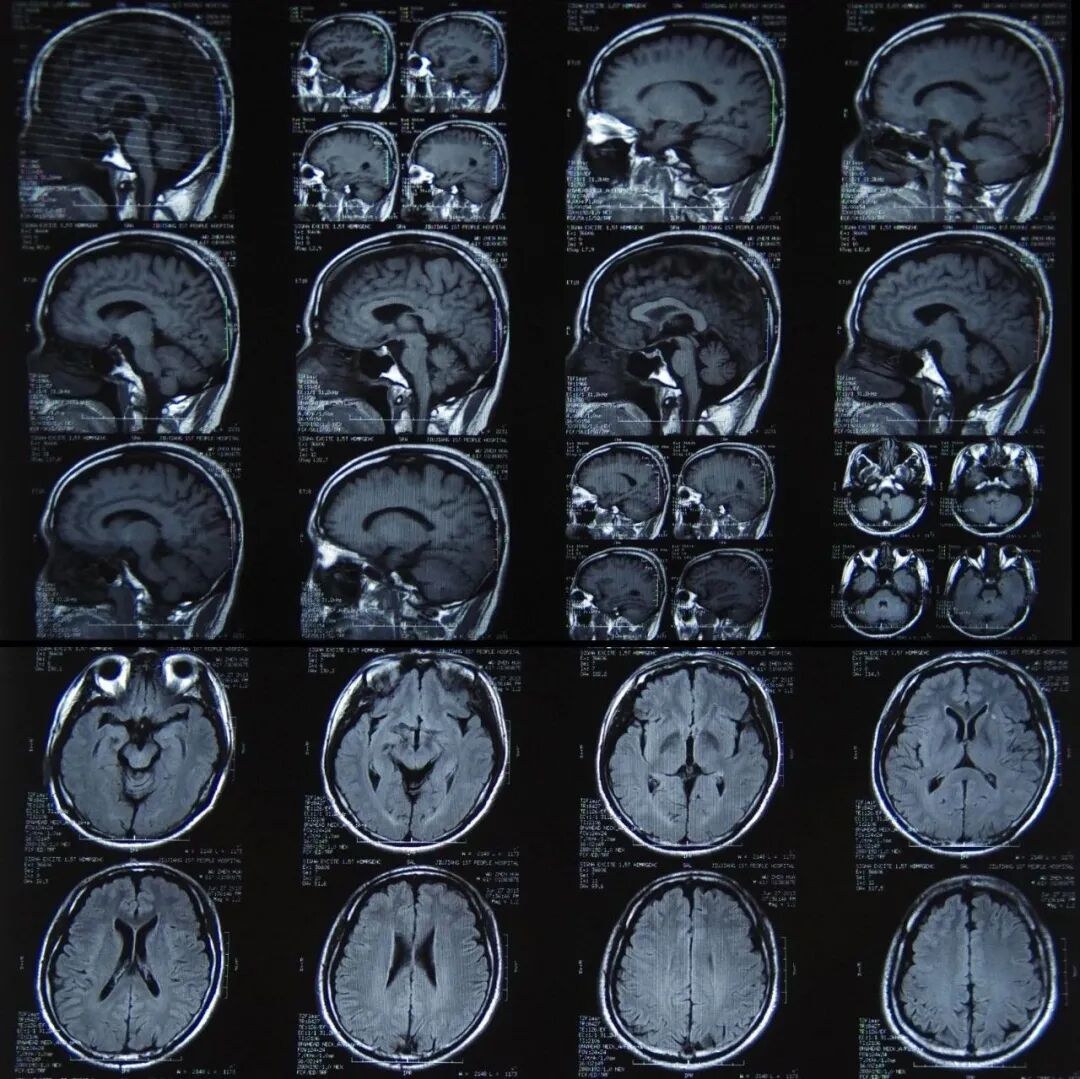

# 核磁(MRI、核磁共振) #

# 核磁共振检查是什么 #

核磁共振成像又称自旋成像,也称磁共振成像,简称MRI,是利用核磁共振原理,依据所释放的能量在物质内部不同结构环境中不同的衰减,通过外加梯度磁场检测所发射出的电磁波,即可得知构成这一物体原子核的位置和种类,据此可以绘制成物体内部的结构图像。

将这种技术用于人体内部结构的成像,就产生出一种革命性的医学诊断工具。快速变化的梯度磁场的应用,大大加快了核磁共振成像的速度,使该技术在临床诊断、科学研究的应用成为现实,极大地推动了医学、神经生理学和认知神经科学的迅速发展。

核磁共振的作用

核磁共振成像是一种利用核磁共振原理的最新医学影像新技术,对脑、甲状腺、肝、胆、脾、肾、胰、肾上腺、子宫、卵巢、前列腺等实质器官以及心脏和大血管有绝佳的诊断功能。

与其他辅助检查手段相比,核磁共振具有成像参数多、扫描速度快、组织分辨率高和图像更清晰等优点,副作用很小,不具有辐射,可帮助医生“看见”不易察觉的早期病变,目前已经成为肿瘤、心脏病及脑血管疾病早期筛查的利器。

2 核磁共振检查注意事项有优缺点?

磁共振成像的优点:

核磁成像的最大优点是它是当前少有的对人体没有任何伤害的安全、快速、准确的临床诊断方法。

具体说来有以下几点:对软组织有很好的分辨力。对膀胱、直肠、子宫、阴道、骨、关节、肌肉等部位的检查比CT优胜;对于椎间盘和脊髓,可作矢状面、冠状面、横断面成像,可以看到神经根、脊髓和神经节等。不像CT只能获取与人体长轴垂直的横断面;

对人体没有电离辐射损伤;

MRI的主要缺点有:

和CT一样,MRI也是解剖性影像诊断,很多病变单凭核磁共振检查仍难以确诊,不像内窥镜可同时获得影像和病理两方面的诊断;对肺部的检查不优于X射线或CT检查,对肝脏、胰腺、肾上腺、前列腺的检查不比CT优越,但费用要高昂得多;对胃肠道的病变不如内窥镜检查;扫描时间长,空间分辨力不够理想;由于强磁场的原因,MRI对诸如体内有磁金属或起搏器的特殊病人不能适用。